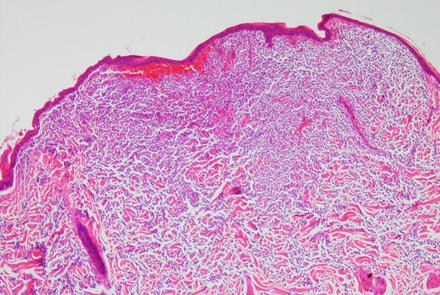

病理組織学的初見では、フェレットのcMCTの細胞質内の顆粒は様々に観察されます。ある研究では、微量の淡く染まる顆粒が認められました〔Kanfer et al.2013〕。別の研究では、cMCT顆粒は組織学的にはヘマトキシリン・エオジン(H&E)染色および結核染色では染色されなかったが、細胞学的には顕著な顆粒として染色されたと報告されています〔,Vilalta et al.2016〕。組織学的なH&E染色やトルイジンブルー(TB)染色で染色性が乏しいにもかかわらず、細胞診では顕著な顆粒が確認されることがあります 。この染色性の低さを踏まえ、臨床医は、顆粒が不明瞭に見える場合であっても、MCTの可能性を性急に排除すべきではありません。